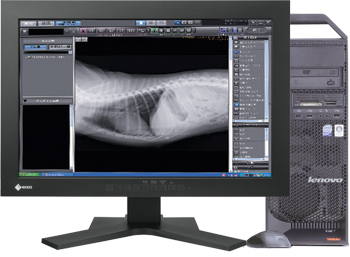

Workstation PACS ImagePilot

ImagePilot è il sistema per la gestione dei digitalizzatori Pegasus e Regius ∑. Sviluppato da Konica Minolta, racchiude in un’unica soluzione tutte le funzionalità di una Workstation PACS e di una console di acquisizione. Semplice e intuitivo, ImagePilot è l’unica vera soluzione “all in one” per l’Imaging veterinario.